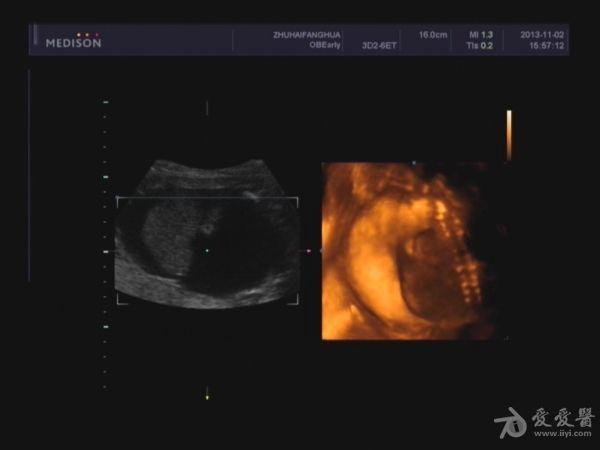

胎儿胸腹腔积液,巨大胎盘。

本帖最后由 jlslst 于 2013-11-2 21:06 编辑 女 25岁,中期孕胎儿产前超声筛查,超声所见:BPD:53mm(22w+1d), H C:212mm(23w+2d),A C:329mm, F L:38mm(23w+0d),HUM:不清,AFD:14mm,AFI:38mm,

单胎妊娠;臀位,颅骨环基本完整,脑中线居中,CER: 24mm,CM:不清,双侧丘脑可见,侧脑室未见明显扩张,小脑可显示欠清,胎儿颈项部欠清,胎儿颜面显示不清,胸腔增大内见积液,腹壁完整,肝、可见,腹腔内大量积液,最大径约:71mm,胸腔内积液最大径:11.4mm,胃及膀胱显示不清。双肾显示不清。双侧四肢长骨显示欠清。

胎盘:附着于子宫后壁,厚度44mm,成熟度:0级,范围面积大,几乎覆着全后壁。

脐带:结构正常,脐动脉血流参数:SPV:33cm/s,PI:1.0,RI:0.62,S/D:2.6。典型图片如下:

诊断意见: 1.宫内中期孕,单胎,胎儿存活,

(根据头围及股骨超声孕周约:22w+3d、胎儿体重约:1256g±)

2.胎儿畸形,胸、腹腔大量积液,

3.超大胎盘,羊水少。

因为羊水少,很多部位观察不清,四维图片基本没意义。期待几天后引产看结果。